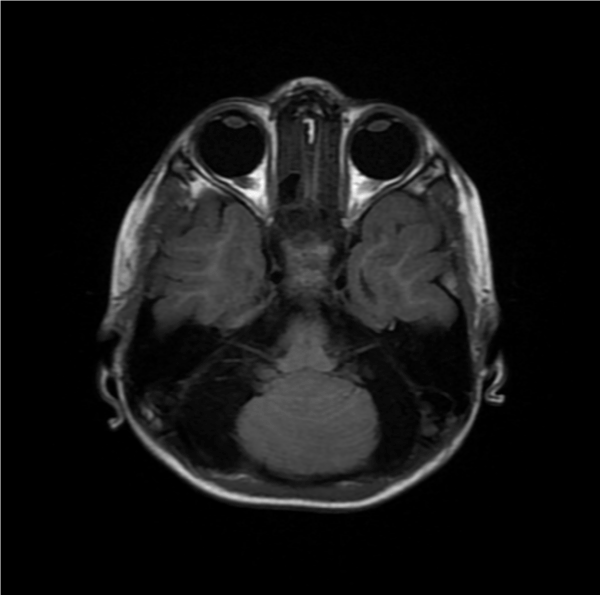

Figure 2. MRI of the posterior fossa demonstrates the absence of the cerebellar vermis with complete fusion of the cerebellar hemispheres Also, notice the absent septum pellucidum giving a mono-ventricle appearance

Figure 4. There is a fusion of cerebellar hemispheres with absent vermis, ventricular prominence without aqueductal stenosis and the absent septum pellucidum giving a mono-ventricle appearance